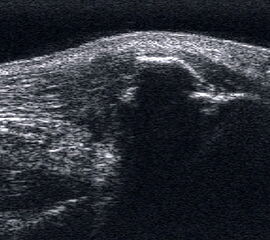

Veränderungen der Strecksehnen

Ruptur der Tibialis anterior Sehne mit retrahiertem Stumpf und umgebendem Hämatom.

Abbildung 49

Lagerung: Rückenlage.

Schnittführung: Ventraler LS und TS über dem OSG und dem Mittelfuß.

Referenzstrukturen: Distale Tibia und Talusrolle, Kahnbein, Cuneiforme-Knochen und Metatarsalia,Sehnen der Mm. tibialis anterior, extensor digitorum longus.

Befunde: Oberhalb der Gelenkkapsel echogene longitudinale parallele Struktur der Strecksehnen. Als dickste Sehne liegt medial die Tibialis-anterior-Sehne, die selten reißt. Die Tibialis anterior Sehne ist als Extensor des Fußes für die Kinematik der Abrollbewegung bedeutsam. Halo-Phänomen und echoarme Verdickung bei zumeist akuter Tendinopathie. Nach Riss oftmals weite Retraktion nach proximal mit umgebender Flüssigkeit oder Hämatom (Abb. 49).